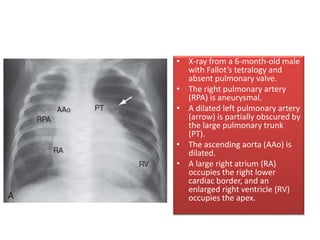

• X-ray from a 6-month-old male

with Fallot’s tetralogy and

absent pulmonary valve.

• The right pulmonary artery

(RPA) is aneurysmal.

• A dilated left pulmonary artery

(arrow) is partially obscured by

the large pulmonary trunk

(PT).

• The ascending aorta (AAo) is

dilated.

• A large right atrium (RA)

occupies the right lower

cardiac border, and an

enlarged right ventricle (RV)

occupies the apex.